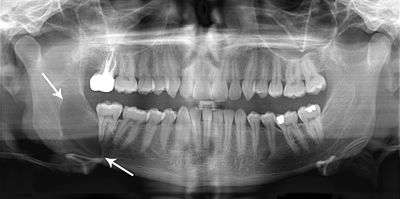

A keratocystic odontogenic tumour (also keratocystic odontogenic tumor, KCOT)[1] is a rare and benign but locally aggressive developmental cystic neoplasm. It most often affects the posterior mandible.

Swelling is the most common presenting complaint; however, KCOTs may be asymptomatic and found incidentally on dental X-rays.[5]